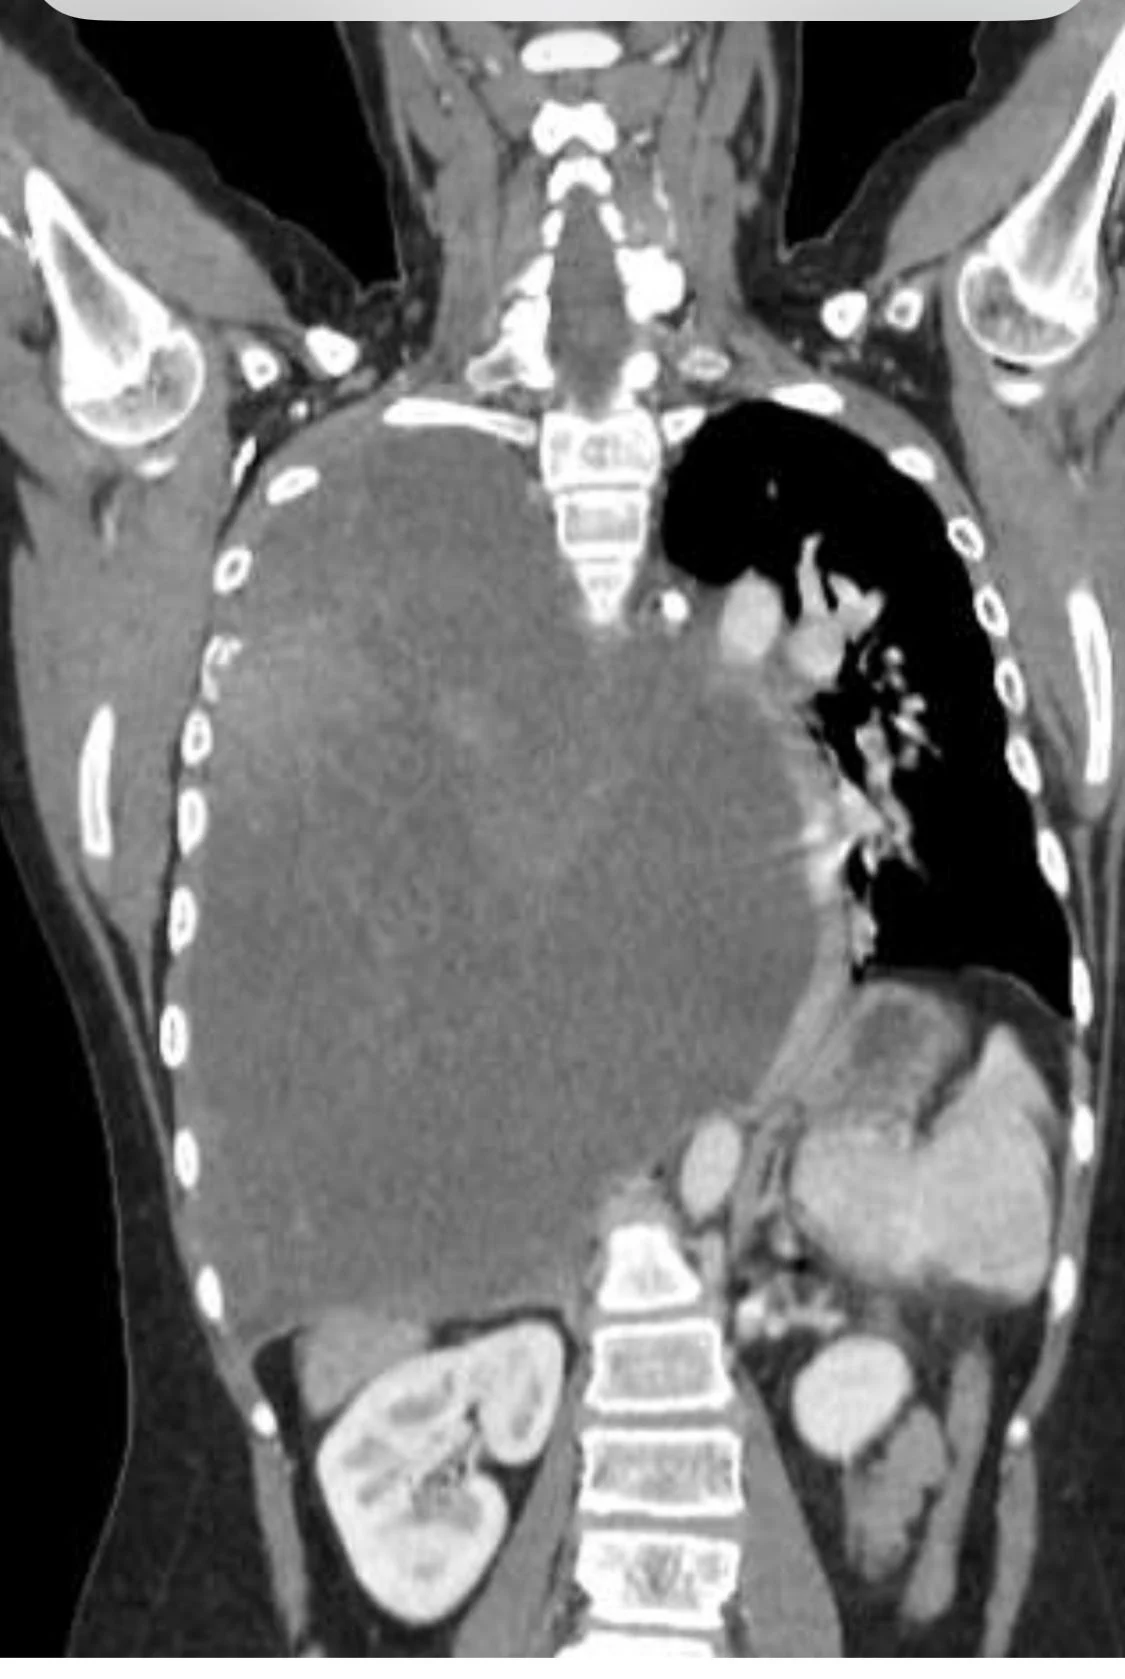

“In my 35 years as an oncologist, I have never encountered such a rapidly progressive case of Sarcoma in a 13-year-old child. This child, who was previously healthy and active, suddenly developed shortness of breath, cough, and rib pain. Imaging revealed that the entire right lung is replaced with a tumor, pushing the heart to the side. Notably, the largest reported Ewing Sarcoma has been less than half the size of this case in terms of 3D dimensions.